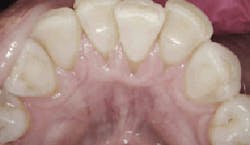

On July 7, 2016, when the patient returned, bleeding was reduced from 101 sites to seven sites, and deep pockets decreased from 37% to just 2%. The patient was then asked to incorporate the trays into her regular home care, using them once a day for 15 minutes.

Taken after probing on July 7, 2016. Image courtesy of Perfect Teeth–Frank Lloyd Wright.